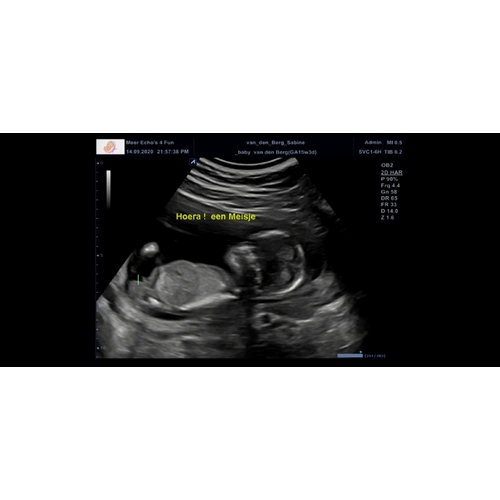

Bij 13w en 5 dagen zag je het ook vanaf zijkant en deze echo is 14w en 6 dagen

Bij 13w en 5 dagen zag je het ook vanaf zijkant en deze echo is 14w en 6 da ...

Ik was daar 14 weken en 6 dagen😊